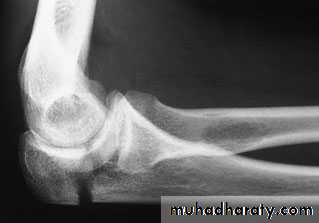

X-ray

1-A comminuted fracture with the triceps intact should be treated as a severe ‘bruise’. Many of these patients are old and osteoporotic, and immobilizing the elbow will lead to stiffness. The arm is rested in a sling for a week; a further x-ray is obtained to ensure that there is no displacement and the patient is then encouraged to start active movements.2-An undisplaced transverse fracture that does notseparate when the elbow is x-rayed in flexion can be treated closed. The elbow is immobilized by a cast in about 60 degrees of flexion for 2–3 weeks and then exercises are begun. Repeat x-rays are needed to exclude displacement.